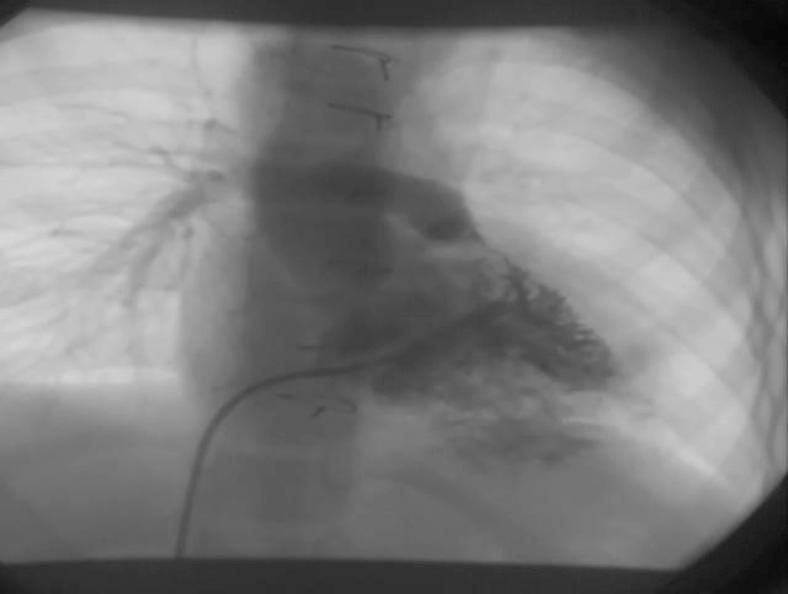

Native right ventricular outflow tract stenting in a child with tetralogy of fallot and absent left pulmonary artery.

Iran J Pediatr. 2014 Feb;24(1):119-21. Epub 2013 Nov 30.

PMID:25793059

原文链接:https://pmc.ncbi.nlm.nih.gov/articles/PMC4359597/

Native right ventricular outflow tract stenting in a child with tetralogy of fallot and absent left pulmonary artery.法洛四联症合并左肺动脉缺如患儿的右心室流出道原位支架植入术

A different therapeutic strategy for severe tetralogy of Fallot with origin of the left pulmonary artery from the ascending aorta: stenting of the right ventricular outflow tract before complete repair.一种针对左肺动脉起源于升主动脉的重症法洛四联症的不同治疗策略:在完全修复前对右心室流出道进行支架置入术。